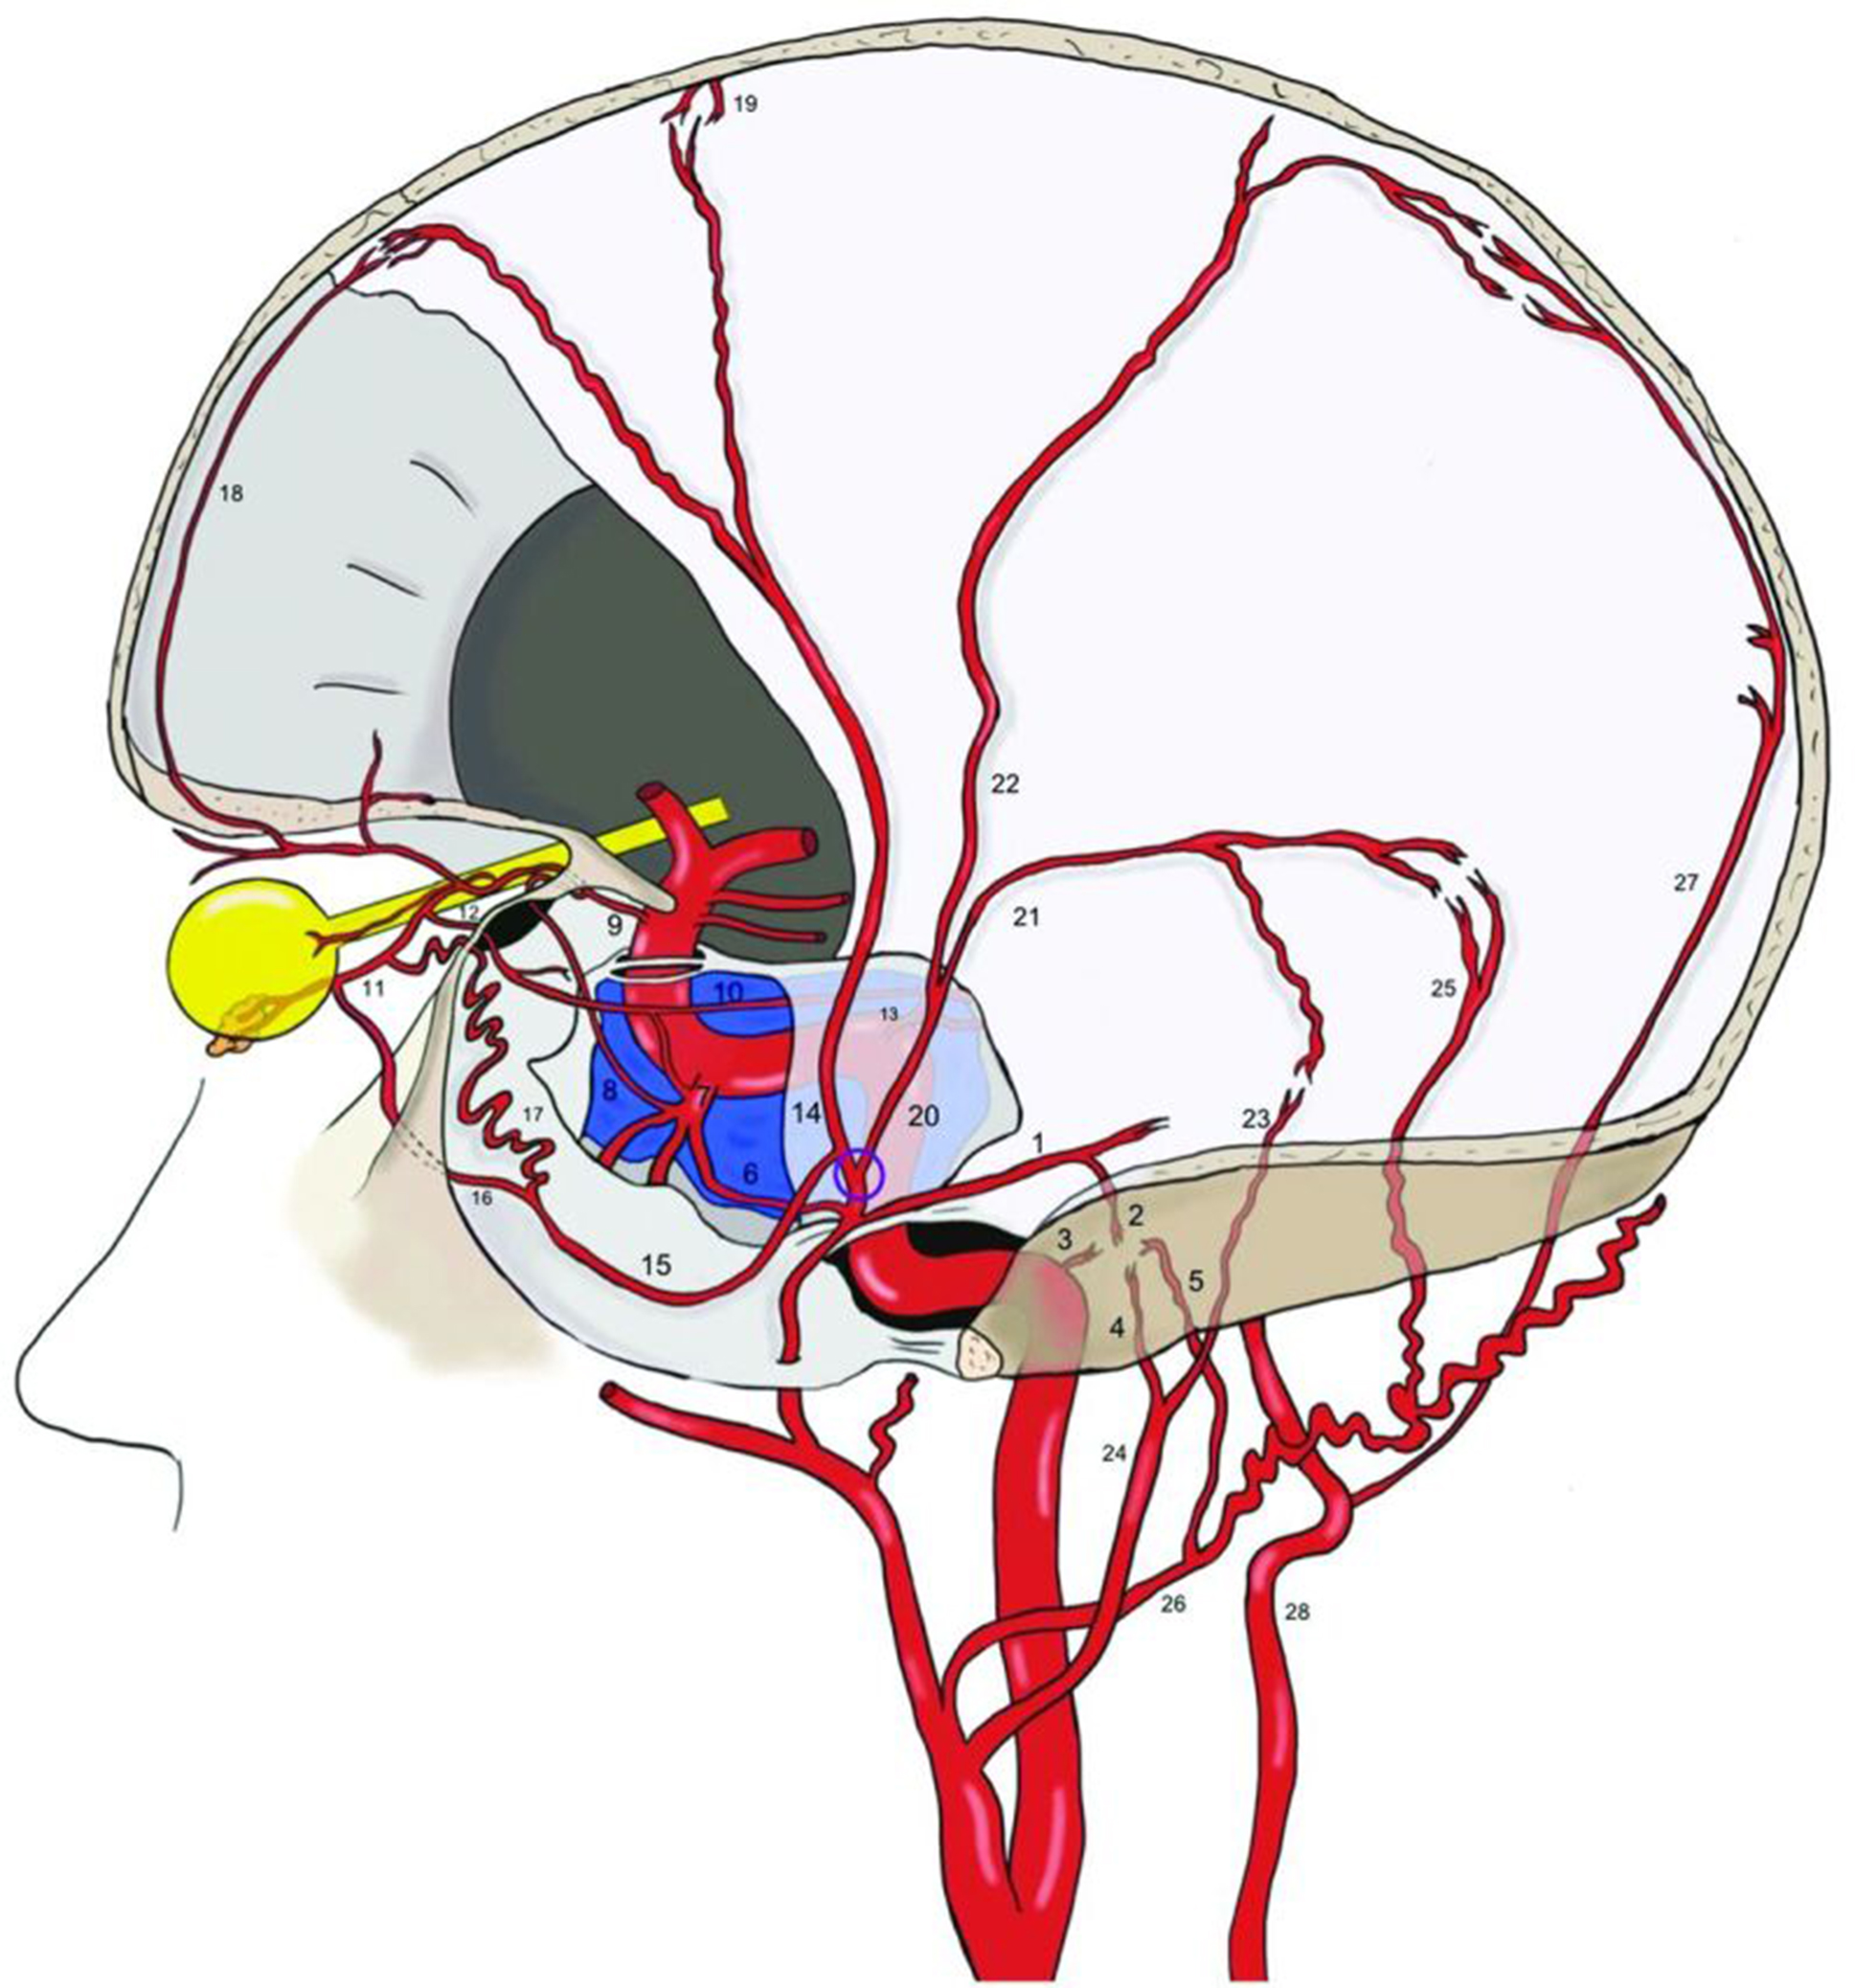

In addition, Onyx™ contains radiopaque components (tungsten or tantalum powder), allowing real-time fluoroscopic monitoring of its injection, as well as the direction of penetration or reflux. This feature is particularly important for preventing intraoperative risks associated with occlusion of “dangerous” anastomoses with the internal carotid and ophthalmic artery territories, as well as blood supply to the myelin sheaths of cranial nerves (Figs. 11B,C and 17).

Fig. 17. Schematic illustration of MMA anastomoses [19]. Before its bifurcation (marked by a purple circle), the petrosal branch (1), from which the superior tympanic artery (2) arises, anastomoses within the middle ear with the caroticotympanic artery (3, from the internal carotid artery), as well as with the inferior tympanic artery (4, from the ascending pharyngeal artery) and the posterior tympanic artery (5, from the occipital artery). On the opposite side, the cavernous branch of the MMA (6) anastomoses with the inferolateral trunk (7) and the meningohypophyseal trunk (13). The inferolateral trunk is connected to the ophthalmic artery (9) via its deep recurrent branch (8). The inferolateral trunk, the MMA, and the ophthalmic artery are also interconnected through the marginal tentorial artery (10), whose origin may vary: from the lacrimal artery (11), via the superficial recurrent branch of the ophthalmic artery (12), or from the meningohypophyseal trunk (13). After bifurcation of the MMA in the pterional region, its frontal branch (14) gives rise to a medial branch (15), which may intracranially divide into the meningolacrimal branch (ramus meningolacrimalis) (16) and the medial sphenoidal artery (17). Both branches connect with the lacrimal artery, although the meningolacrimal artery arises more distally than the sphenoidal branch. Anastomoses with the ophthalmic artery and the inferolateral trunk are the most dangerous during transcatheter MMAe due to the risk of embolization of these arteries. The frontal branch of the MMA reaches the convexity surface along the coronal suture and anastomoses with the anterior falcine artery (18, a branch of the ophthalmic artery—the anterior ethmoidal artery) and with branches of the contralateral MMA (19). The posterior branch of the MMA (20) divides into the petrosquamous branch (21) and the parieto-occipital branch (22). The former anastomoses with the jugular branch (23) of the ascending pharyngeal artery (24) and with the mastoid branch (25) of the occipital artery (26). The latter is connected with the posterior meningeal artery (27), arising from the vertebral artery (28) in the border zones

The middle meningeal artery has numerous anastomoses with branches of the internal carotid, ophthalmic, occipital, and ascending pharyngeal arteries. Knowledge of the topography and variability of these anastomoses is crucial for the safe performance of embolization, reduction of neurological complication risk, and improvement of treatment efficacy in cSDH.